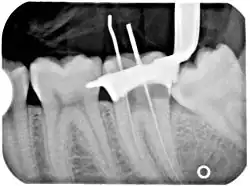

An x-ray of a root canal operation

An X-ray explanation of bad root canal therapy

X-ray explanation of bad root canal therapy

Another common complication of root canal therapy is when the entire length of the root canal is not completely cleaned out and filled (obturated) with root canal filling material (usually gutta percha). On the other hand, the root canal filling material may be extruded from the apex leading to other complications. The X-ray in the right margin shows two adjacent teeth that had received bad root canal therapy. The root canal filling material (3, 4, and 10) does not extend to the end of the tooth roots (5, 6 and 11). The dark circles at the bottom of the tooth roots (7 and 8) indicated infection in the surrounding bone. Recommended treatment is either to redo the root canal therapy or extract the tooth and place dental implants. Poor quality filling material or sealant may also cause root canal treatment to fail.[48]